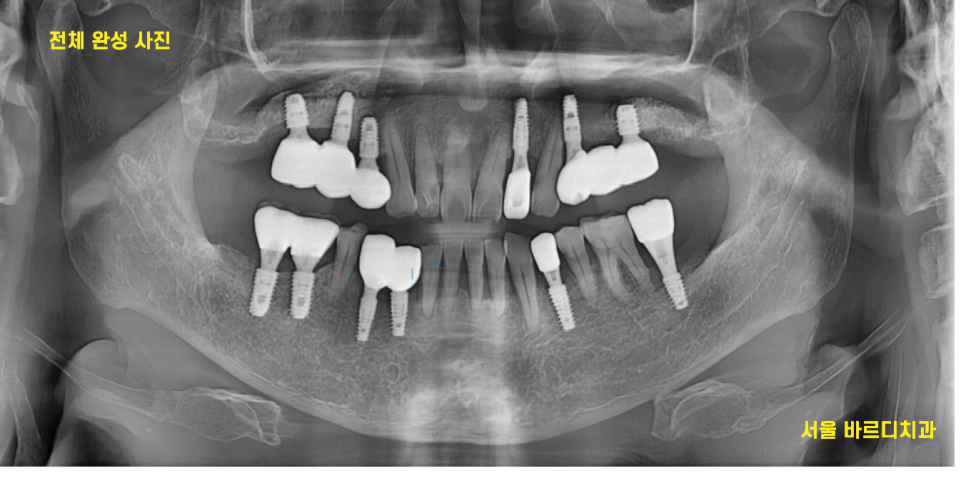

23.11.03

뼈가 좋은 오른쪽 먼저 치아를 완성했습니다.

기존 1개 살린 임플란트와

임플란트 제거 후 재식립한 부분을 연결하여

완성했습니다.

24.01.22

뼈가 약해서 조금 더 기다린 오른쪽도

마저 완성을 한 모습입니다.